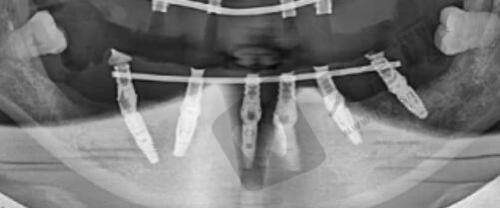

典型实例显示,采用Motiva假体的顾客满意度达98%,其中85%的实例在术后3个月即实现理想胸型。医院配备的4D内窥镜系统,可实时监控假体植入角度,确保双侧对称度误差小于0.3cm。

白云区曙光医院2025年引进第五代威塑VASER系统,其钛金属探头能精细乳化脂肪细胞,对血管和神经的损伤率降至0.8%。腰腹环吸项目采用\"三区九点\"定位法,单次手术可安心抽取3000-4500ml脂肪。